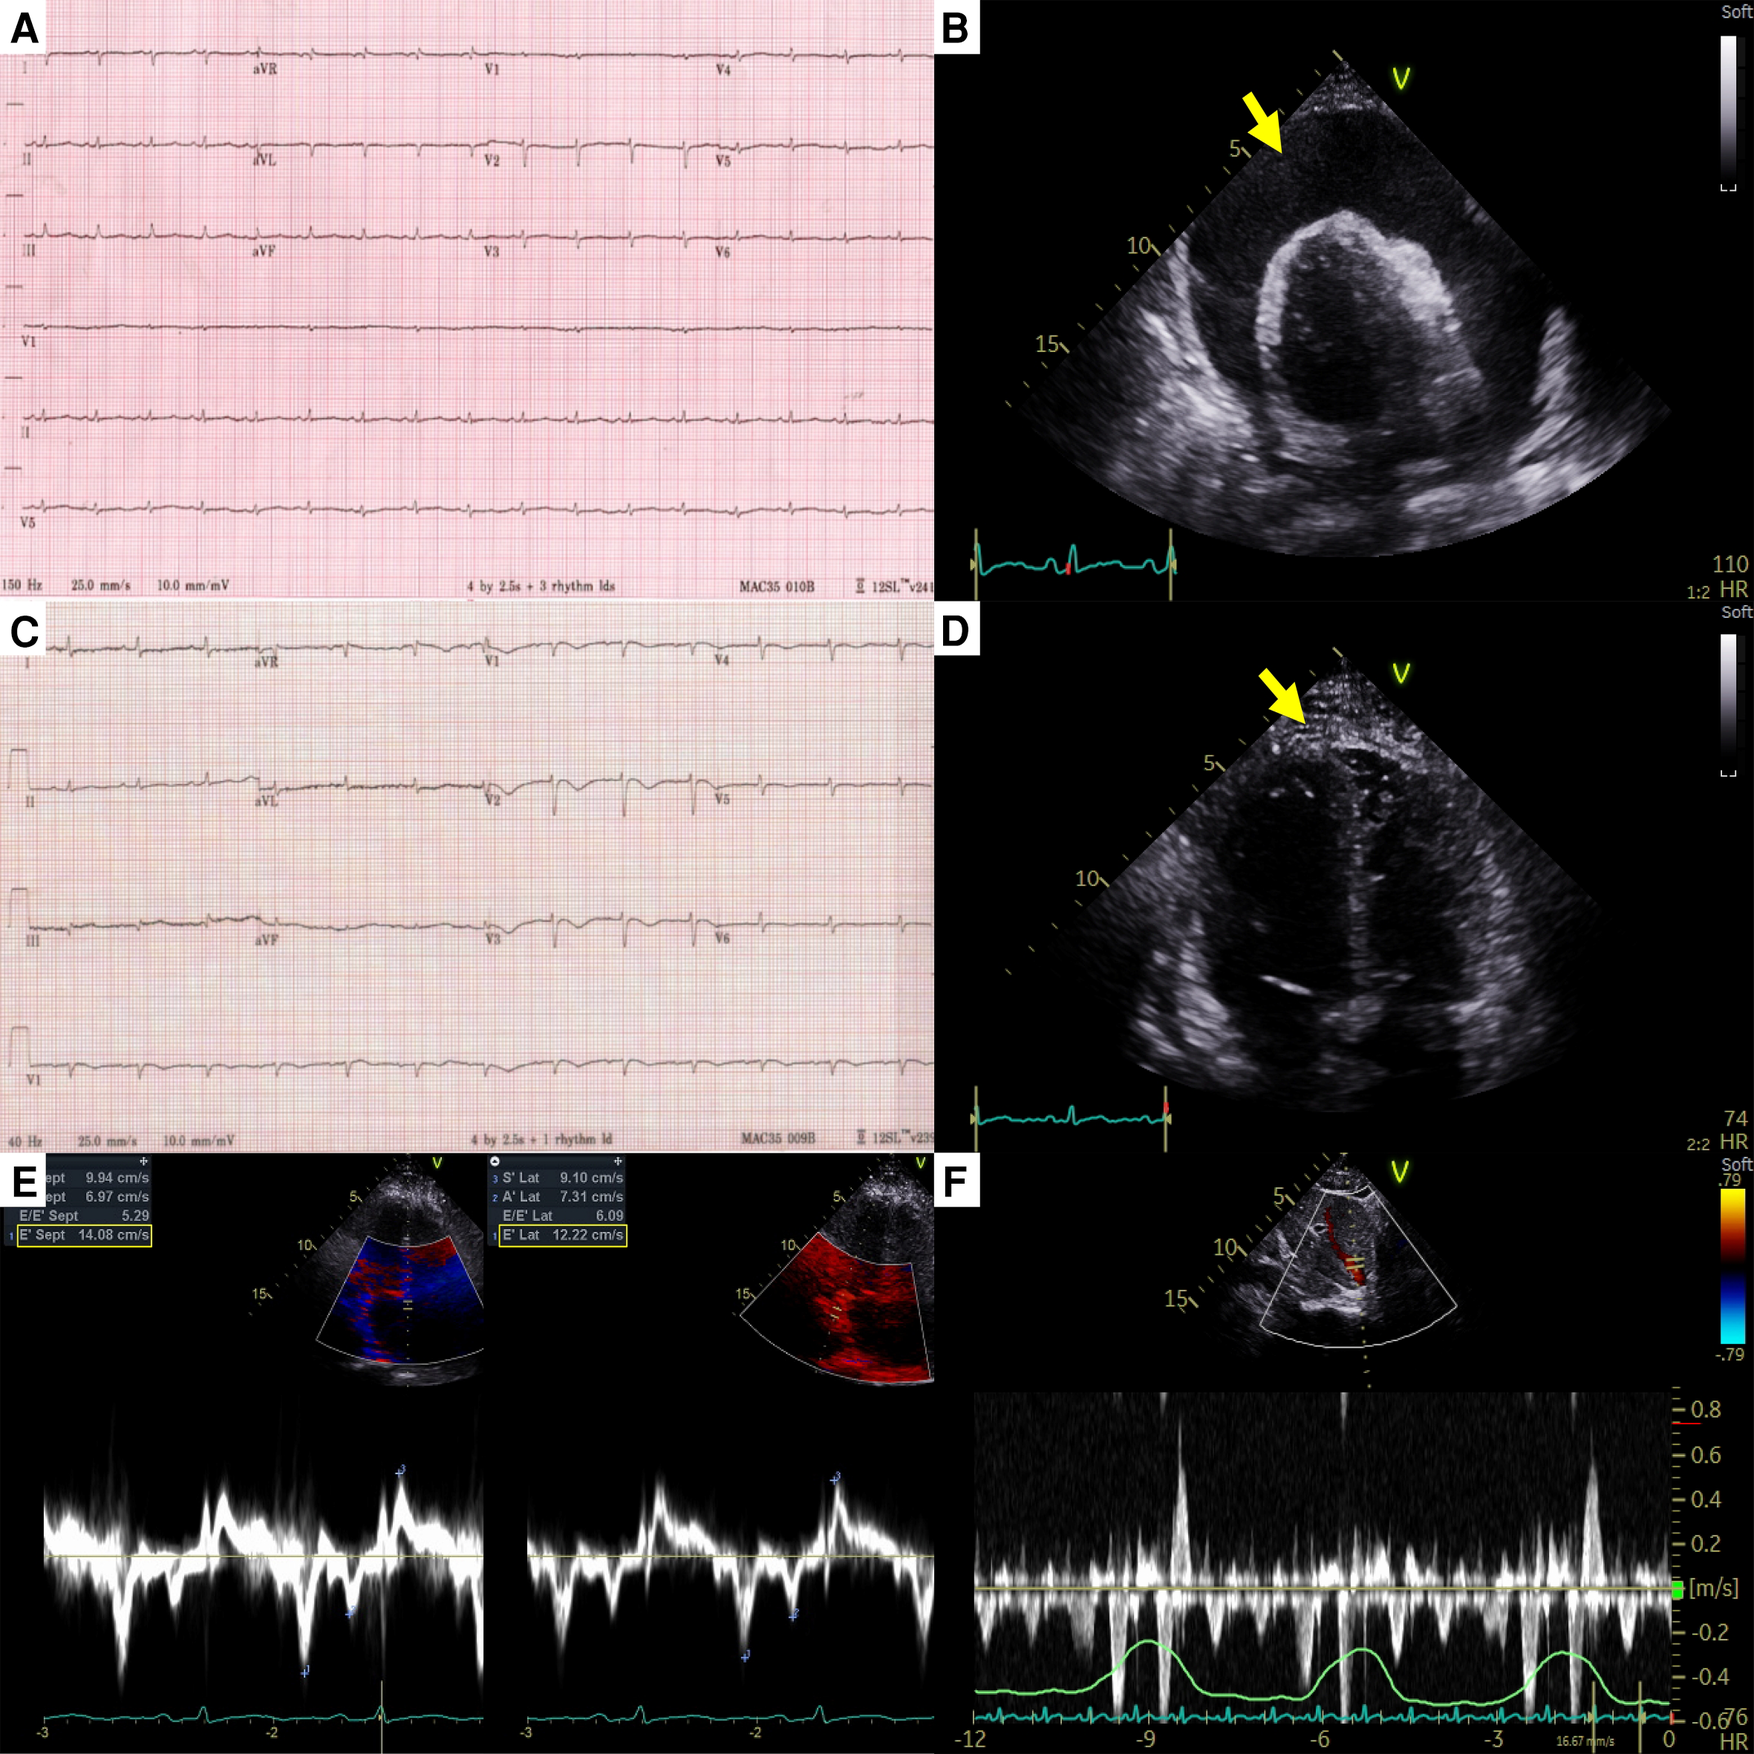

A 44-year-old female patient who had been undergoing 65 cycles of palliative chemotherapy with trastuzumab and pertuzumab for human epidermal growth factor receptor 2 (HER2)-positive MBC presented to the emergency department with dyspnea. The patient's blood pressure was 101/69 mmHg, and her pulse rate was slightly high at 105 beats per min (BPM). Initial electrocardiography (ECG) revealed a low-voltage QRS complex (Figure 1A), and her N-terminal pro-brain natriuretic peptide (NT-proBNP) level was relatively low (424 pg/ml). Therefore, we suspected cardiac tamponade and promptly performed echocardiography. A large PE with definite tamponade physiology was observed (Figure 1B, Supplementary Video 1), and emergent pericardiocentesis was performed. The next day, the ECG revealed a newly developed anterior T wave inversion (Figure 1C). Follow-up echocardiography showed markedly reduced PE, disseminated pericardial adhesions, and thickening with CP, suggesting effusive-constrictive pericarditis (ECP) (Figures 1D–F, Supplementary Video 2). Two days after pericardiocentesis, her dyspnea and tachycardia did not fully resolve, and the NT-proBNP level was elevated to 1,680 pg/ml, all of which were compatible with ECP. AIT against ECP was initiated using with prednisolone (started with 0.5 mg/kg/day, gradually tapered for 2 months) and colchicine (0.6 mg/day). A metastatic adenocarcinoma was identified on cytopathology in the drained PE, whereas no other possible causes of PE were identified in either serologic or PE analyses. Owing to the positive result of pericardial fluid cytopathology, we judged her breast cancer as a progressive disease and decided to change the cancer therapy to trastuzumab emtansine (T-DM1). However, cardiac tamponade recurred twice (2 and 5 months after initial pericardiocentesis, respectively), even after switching to T-DM1 (Figures 2A,B, Supplementary Videos 3 and 4), while other metastatic sites remained stable. Repeated pericardiocentesis and AIT for ECP were performed for each episode of cardiac tamponade. Despite recurrent cardiac tamponade episodes with T-DM1 therapy, we continued T-DM1 therapy with AIT because the symptoms and signs of heart failure were well controlled after pericardiocentesis and AIT. Furthermore, the oncological response to T-DM1 was thought to be stable, except for recurrent PE. Finally, after three times of pericardiocenteses, AIT, and eight cycles of T-DM1 therapy, cardiac tamponade has not recurred until now. The patient has been on T-DM1 maintenance therapy with an oncologic state of stable disease for two years.

Figure 1

Electrocardiography and echocardiography at the first cardiac tamponade episode in case 1. (A) Low-voltage QRS complex in initial electrocardiography. (B) Large pericardial effusion (arrow) causing cardiac tamponade. (C) Newly developed anterior T wave inversion in post-pericardiocentesis electrocardiography. (D) Diffuse pericardial adhesions, and thickening (arrow) in post-pericardiocentesis echocardiography. (E) The medial early diastolic tissue doppler velocity exceeding the lateral velocity (annulus reversus). (F) Prominent expiratory diastolic flow reversal in the hepatic vein. Both (E) and (F) are suggestive of constrictive physiology.